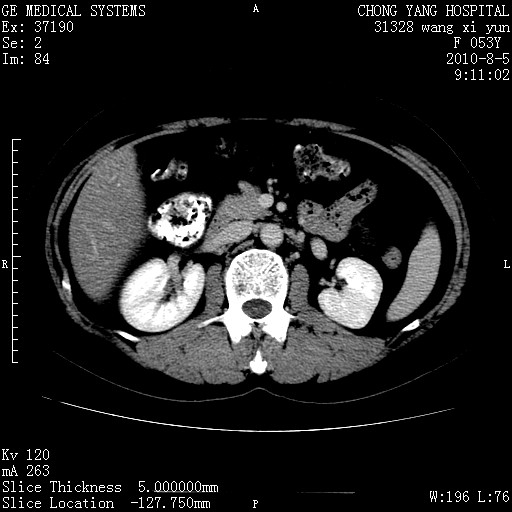

标题: CT28214:F41Y 血尿二十天,建议盆腔平扫加增强。

1)考虑肝左叶胆管细胞癌。2)脂肪肝。